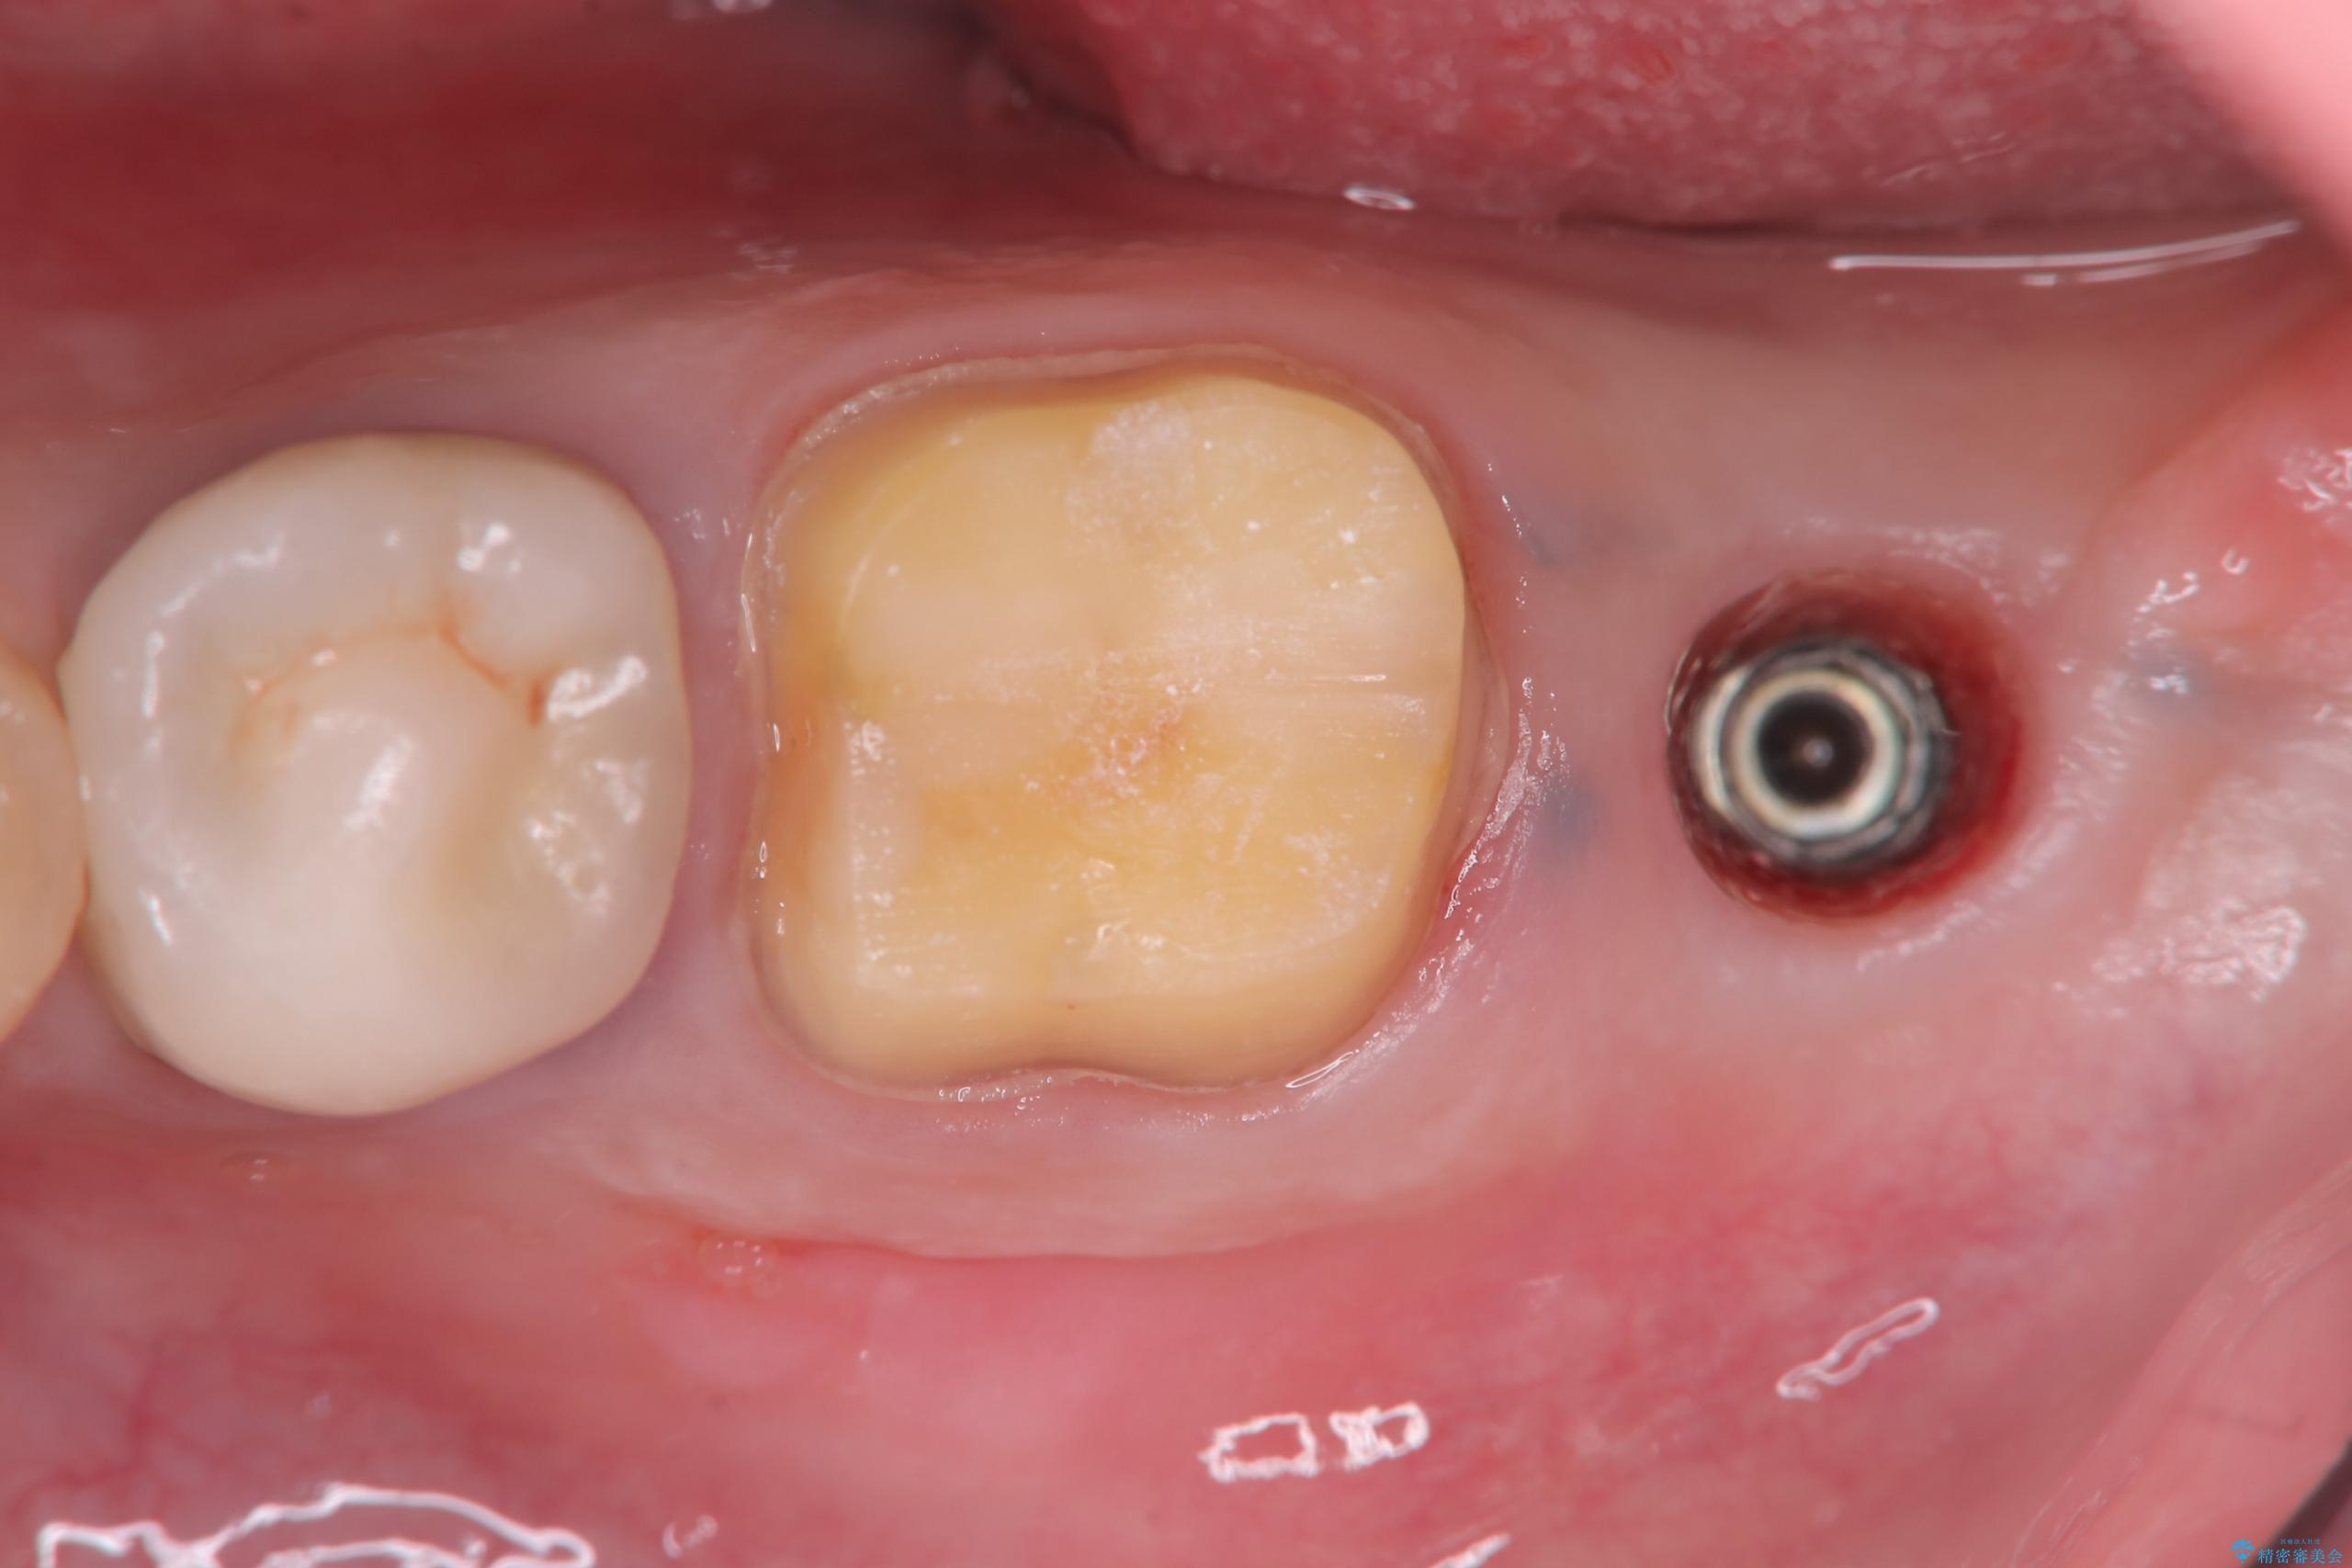

- 過去にヘミセクションが行われていたと思われる左下7番は、大きな歯根嚢胞および根尖病変が認められ、さらに骨縁下カリエスを伴っており、歯肉には瘻孔が形成されている状態でした。

保存は困難と判断し、左下7番は抜歯即時インプラントによる治療を行いました。

抜歯と同時にインプラントを埋入するため、歯茎を切開する必要がなく、術後の痛みが出にくい治療方法です。